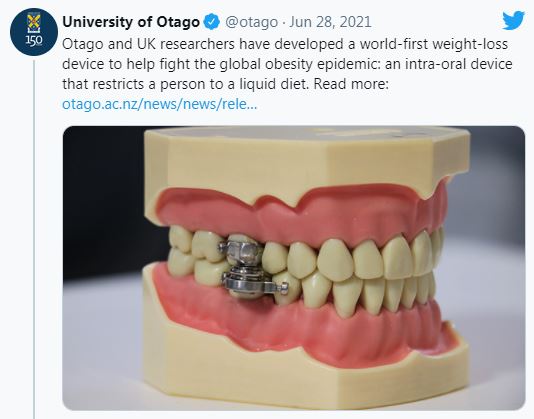

「這是世界上第一個能對抗胖症的減重裝置」奧塔哥大學研究團隊在推特上強調,英國牙科雜誌 (British Dental Journal) 上刊登了這個減重裝置的實驗結果,發現受試者平均都減去了5%體重。

圖片來源 / University of Otago,下同